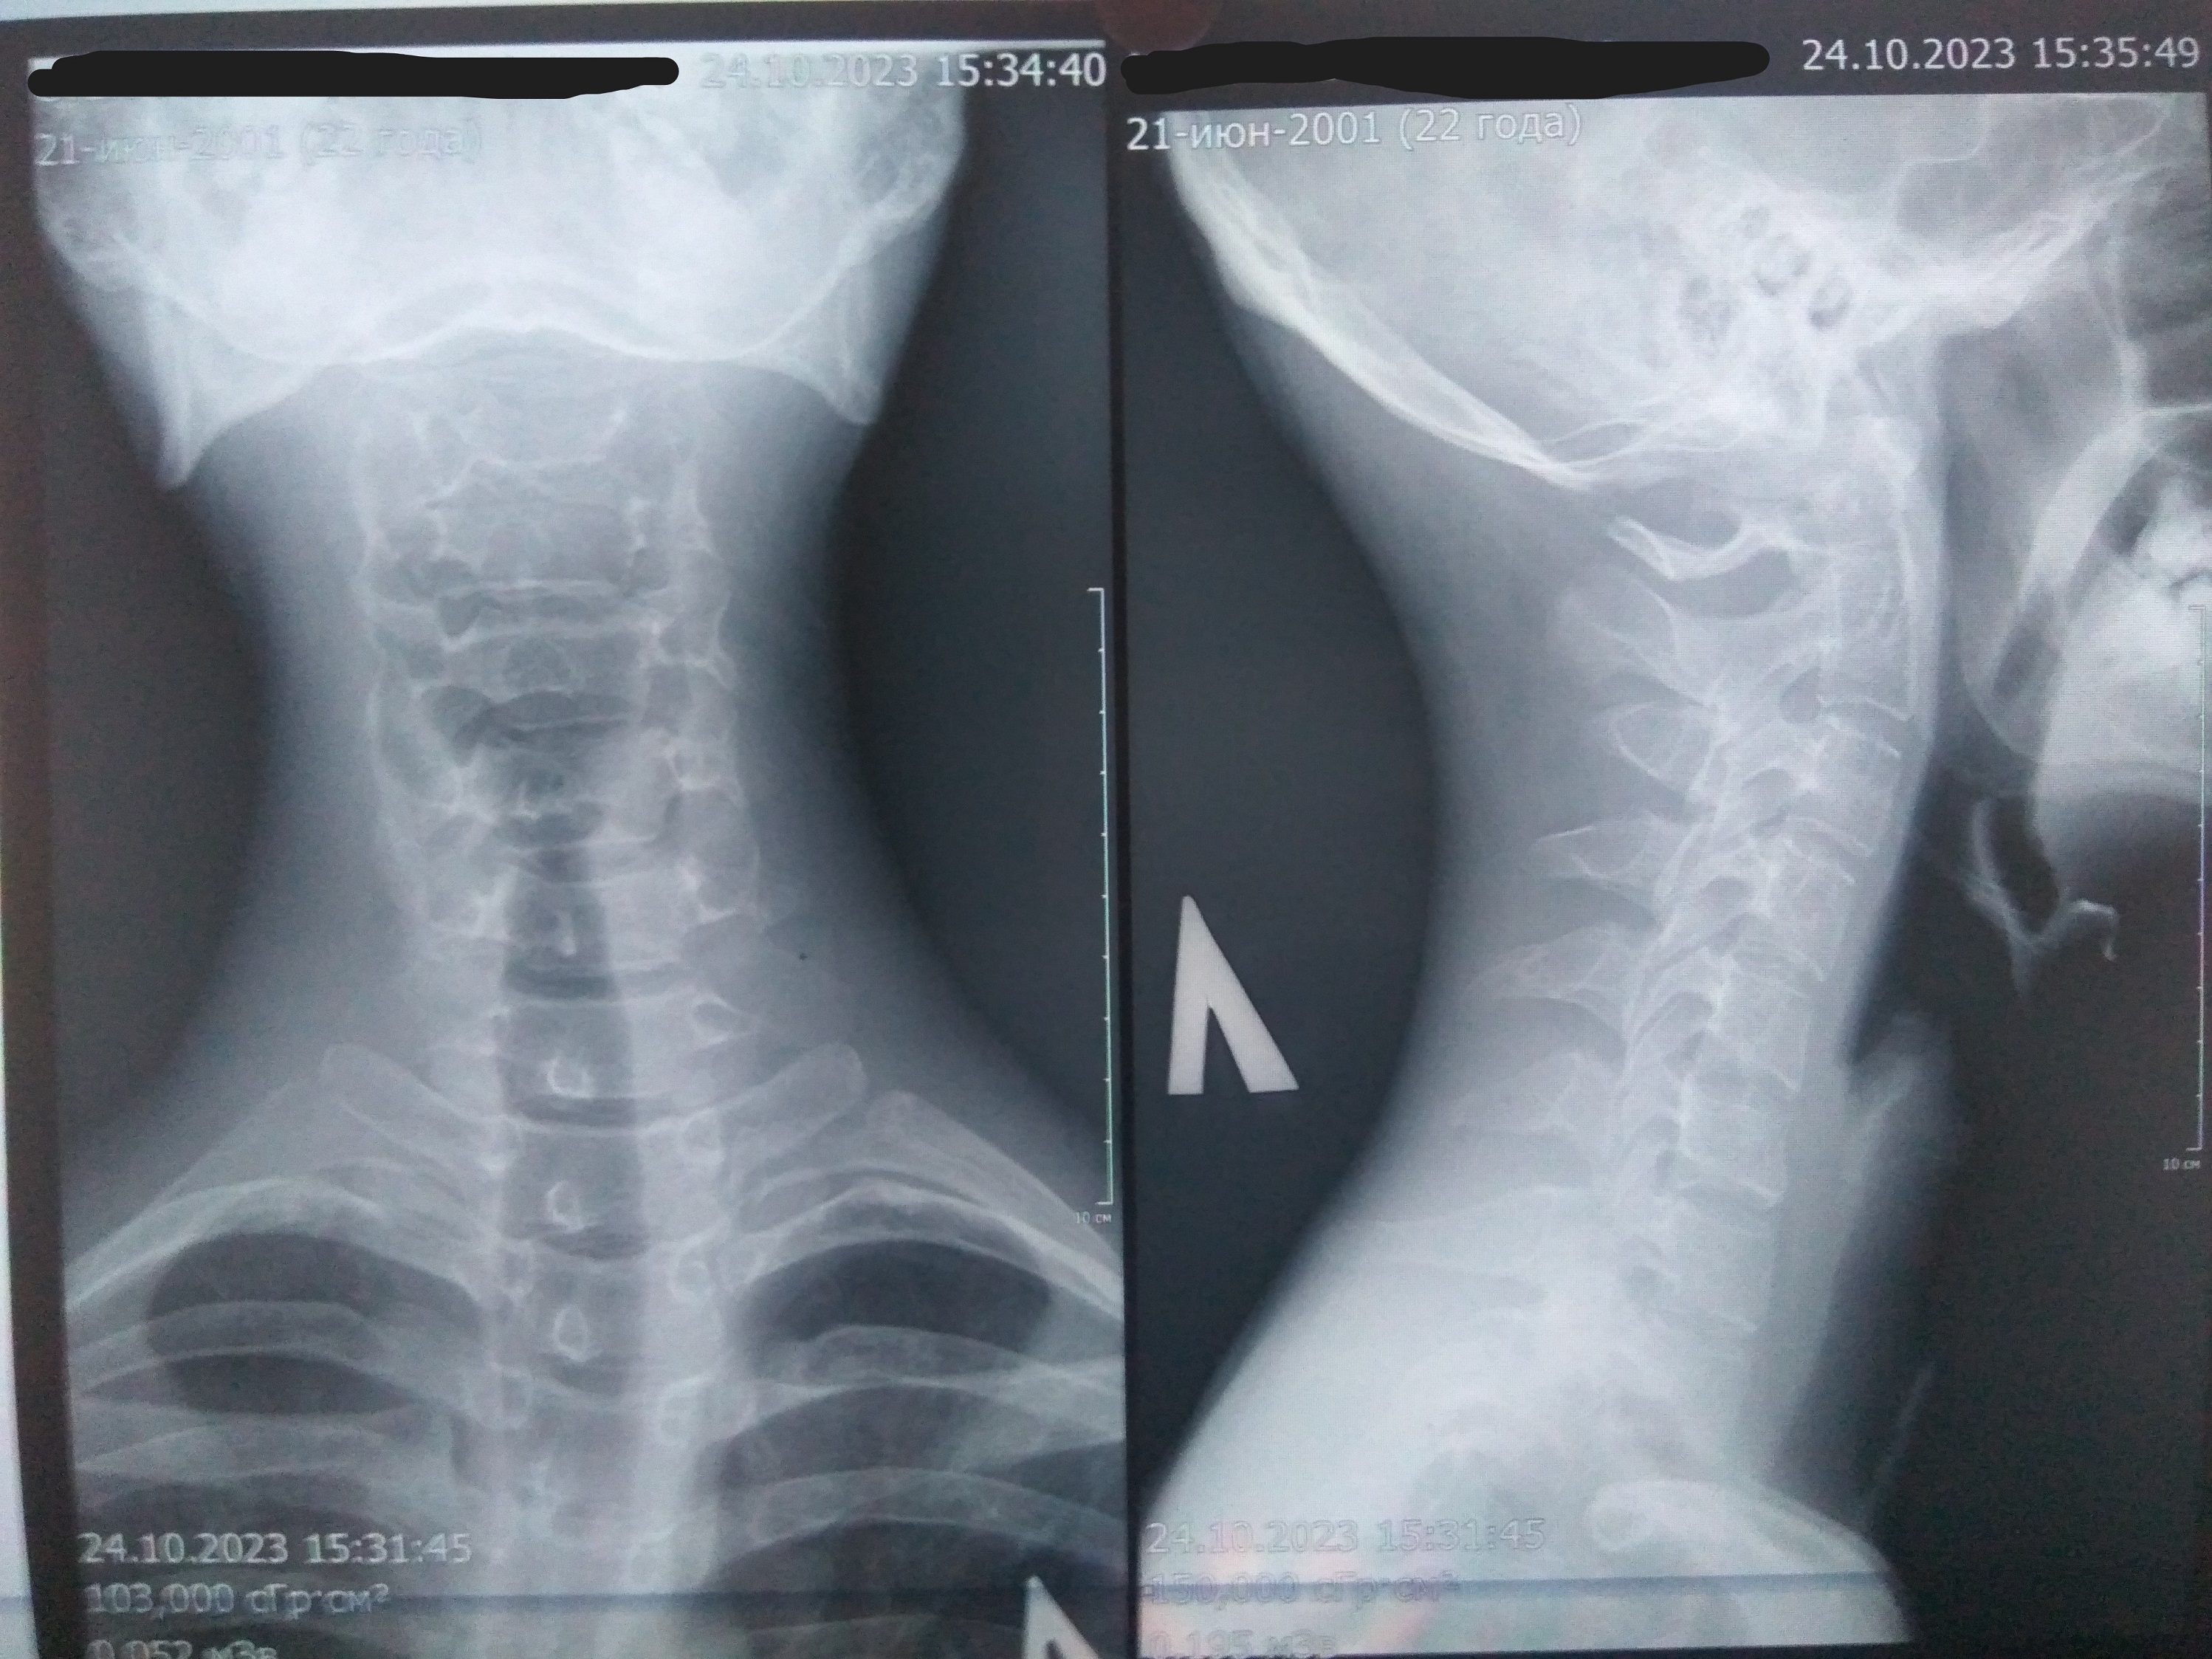

На днях ещё раз сходил к неврологу, и вот результат рентгена шеи в 2 стандартных проекциях (от 24 октября 2023; один снимок с запрокинутой головой назад с передней стороны, а второй - обычное положение, но с правого бока):

"Физиологический лордоз сглажен, выпрямлен на уровне С5-С7; ось отклонена вправо.

Определяется начальное снижение высоты мпд С4-С5. Суставные отростки б/о. Заострение полулунных отростков на уровне С4-С6. Неполная аномалия Киммерли С1.

Заключение: Rg начальные признаки ДДЗП ШОП: остеохондроз межпозвонковых дисков, артроз унковертебральных сочленений. Нарушение статики. Неполная аномалия Киммерли С1."

Вот последний снимок шеи:

IMG_20231105_173611_GC5.1m_1.jpg